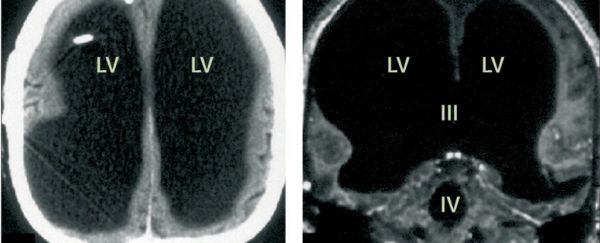

În anul 2007, medicii au descoperit un pacient francez fără 90% din creier. Puteţi vedea mai jos cum arată creierul acestuia.

Radiografia craniană a pacientului fără 90% din creier. Credit: Feuillet et al. /The Lancet

Radiografia craniană a pacientului fără 90% din creier. Credit: Feuillet et al. /The Lancet

Francezul avea 44 de ani în momentul în care studiul de caz al medicilor cu privire la starea sa a fost publicat, pentru prima dată, în The Lancet, iar acesta a trăit până atunci o viață relativ normală, fără să bănuiască că o mare parte din creierul său lipsea. El a avut un loc de muncă, a fost căsătorit și a avut copii. Singurul indiciu că era ceva în neregulă cu el a fost IQ-ul lui ceva mai mic.

Rămâne un mister cum a trăit acest om fără 90% din creier fără a avea simptome specifice, dar cercetătorii au sugerat că distrugerea celei mai mari părţi din creierul său s-a produs treptat, datorită acumulării de lichid în creier, iar neuronii rămaşi par să fi fost în măsură să-i asigure o viaţă normală.

Acest caz reprezintă o provocare pentru oamenii de știință care trebuie să reanalizeze conceptul de conştiinţă, pentru că dacă un om cu doar 10% din creier poate fi conștient de propria sa existență, atunci aceasta sugerează că conștiința nu este localizată fizic în creier.